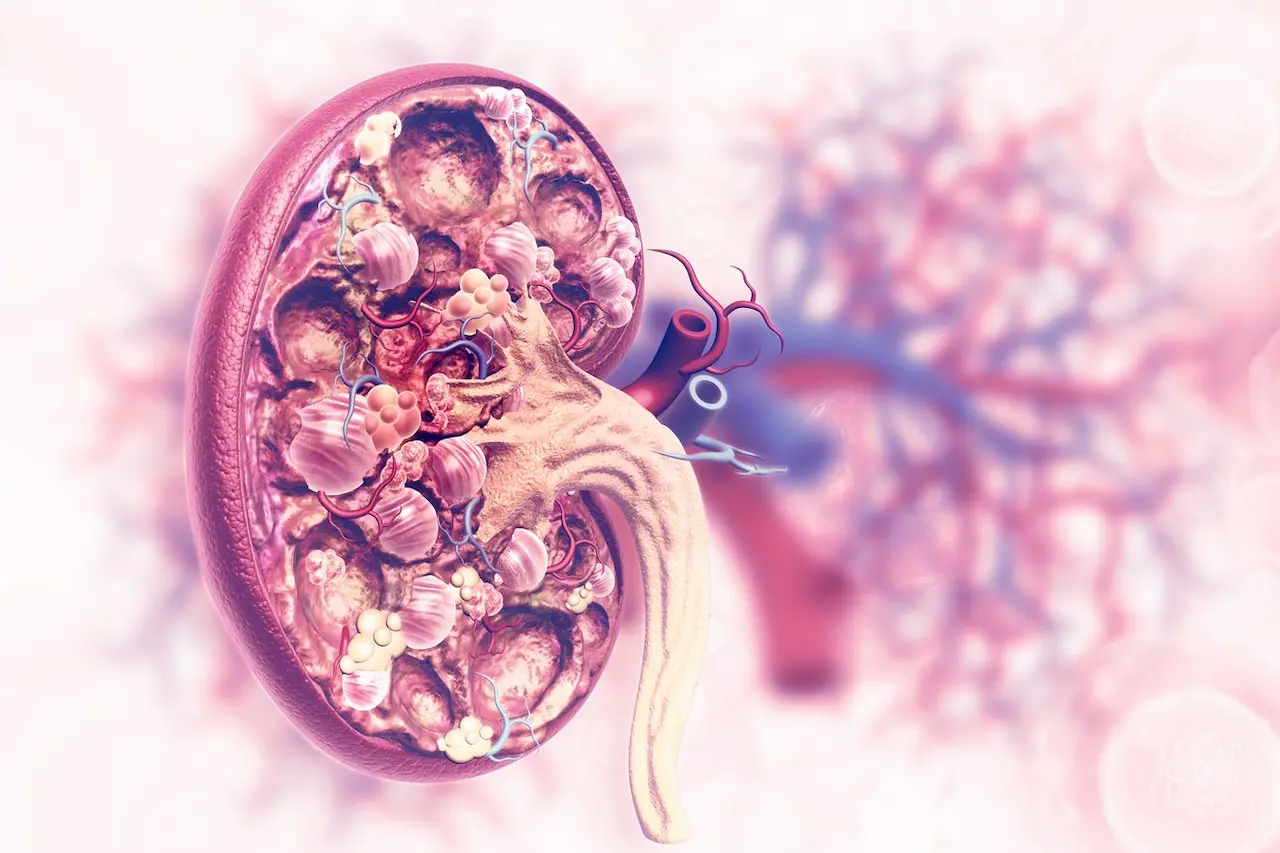

What does fibrosis do to Our Kidneys?

Fibrosis occurs when normally functioning kidney cells are replaced with fibrous connective tissue, similar to scar formation in other parts of the body. It involves an accumulation of excess extracellular matrix, primarily collagen, and usually results in the loss of function when the normal tissue is replaced with scar tissue. Different mechanisms are responsible for kidney fibrosis.

KD derives from a diverse range of aetiologies, including immunological, mechanical, metabolic and toxic insults…this list is not exhaustive! All of these affect the three compartments of the kidney: the vasculature, glomerulus and tubulointerstitium. It is these compartments that are responsible for the delivery of blood, plasma filtration and modification of glomerular filtrate. Even though matrix synthesis is part of the normal repair process, which occurs after injury, excessive synthesis of the extracellular matrix is destructive and further exacerbates injury, becoming a vicious cycle.